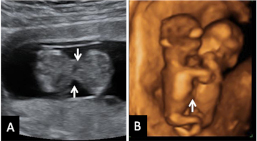

Ecografía 4D de feto de 12 semanas de espaldas

La curiosa ecografía de este feto de 12 semanas comienza con la imagen de espaldas. El niño se gira hasta colocarse de perfil y es entonces cuando empieza a mover brazos y piernas con agilidad. Todo un signo de bienestar fetal.